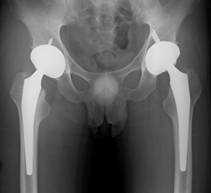

軟骨というクッションがすり減ってしまい、骨に負担がかかって痛い股関節や膝関節を新しい人工の関節に取り換える手術です。歩く時の痛みをなくすだけでなく、かなり変形してしまった関節でも,ほとんど正常に近い機能まで回復させることが可能です。手術後も激しいスポーツ以外は制限しておりませんので、ウォーキングはもちろん、自転車、ゴルフなども可能です。

もともと股関節の屋根が少ない方(臼蓋形成不全)などに対して、骨を移動させることで屋根を作る手術も可能です(臼蓋棚形成術など)。

膝の場合には内側の軟骨がすり減りやすくO脚が進んでしまうので、脛骨というスネの骨を矯正することでO脚を直し、痛みを取る手術も行なっています。